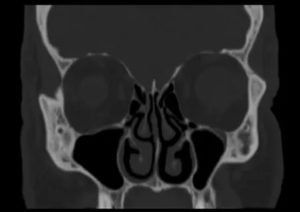

Отвечая на вопрос, что лучше – рентген или КТ пазух носа, необходимо отметить, что компьютерная томография более информативна, поэтому ее назначают, если традиционный рентген не прояснил картину заболевания. Более того, КТ лучше подходит для диагностики гнойной, катаральной и серозной формы гайморита.

Эта процедура дает широкие возможности для постановки и подтверждения различных заболеваний околоносовых синусов. Полученные снимки (рентгенограммы) помогают врачам визуализировать и рассмотреть такие анатомические части: лобные, гайморовые (верхнечелюстные) пазухи, решетчатый лабиринт, глазницы и кости лицевого черепа.

Эта методика позволяет визуализировать патологическое содержимое в околоносовых синусах, изменения слизистой оболочки, выстилающей пазухи (отечность, полипы и другие). В норме околоносовые пазухи заполнены воздухом и не отличаются от глазниц.

Если в них есть жидкость (гной, кровь и др.), образуются затемнения (снижение пневматизации) с горизонтальной верхней границей.

Рентгенографический снимок не является уникальной процедурой. Сегодня её с успехом заменяют на компьютерную томографию или магнитно-резонансную томографию. Оба эти исследования помогают визуализировать труднодоступные места лицевого скелета и увидеть патологии. Во многих случаях КТ и МРТ даже более информативны, нежели рентген ОНП.